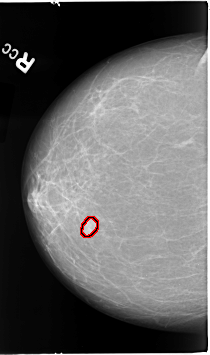

FILE: B_3067_1.RIGHT_CC.OVERLAY

TOTAL_ABNORMALITIES 1

ABNORMALITY 1

LESION_TYPE MASS SHAPE LOBULATED MARGINS CIRCUMSCRIBED-ILL_DEFINED

ASSESSMENT 4

SUBTLETY 5

PATHOLOGY MALIGNANT

TOTAL_OUTLINES 1

BOUNDARY